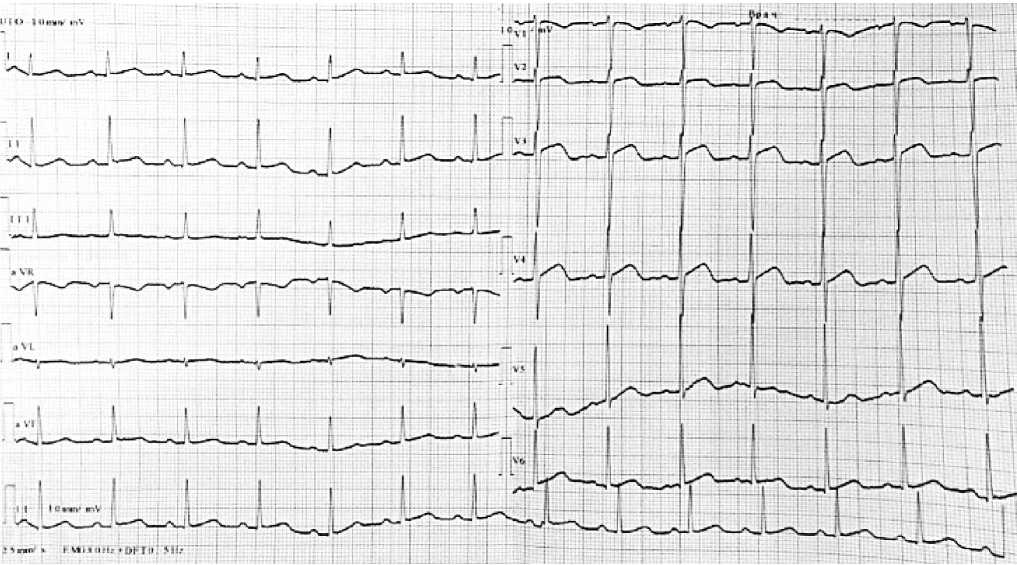

При поступлении : общее состояние пациента расценено как крайне тяжёлое. Сознание ясное, на вопросы отвечает адекватно, но с некоторым замедлением. Кожные покровы и видимые слизистые оболочки бледные, с незначительным иктеричным оттенком. Отмечается выраженное набухание шейных вен, пастозность голеней и стоп. Частота дыхания — 26 в минуту. Сатурация кислорода на атмосферном воздухе в покое — 87-88%. При аускультации — незвучные влажные хрипы в нижних отделах лёгких. Частота сердечных сокращений (ЧСС) — 86 в минуту, артериальное давление (АД) — 120/80 мм рт. ст. Границы относительной сердечной тупости смещены влево на 1 см от средней ключичной линии. I тон на верхушке сердца ослаблен. Живот мягкий, безболезненный при пальпации. Печень безболезненная, не выступает из-под края рёберной дуги. Селезёнка не увеличена. Почки не пальпируются. Симптом поколачивания по поясничным областям отрицательный. По данным ЭКГ от 29.04.2025 — умеренная синусовая тахикардия, подъём сегмента S-T в отведениях, отражающих переднюю стенку левого желудочка (Рисунок 1).

Рисунок. Электрокардиография пациента А., 38 лет

Важно учитывать, что изменения в конечной части комплекса QRS свидетельствуют о массивном поражении миокарда и нарастающей сердечной недостаточности. У нашего пациента на ЭКГ регистрировалась умеренная синусовая тахикардия и незначительный подъём сегмента ST по передней стенке ЛЖ (Рисунок 1). Эти изменения, а также повышение уровня тропонина I при остром миокардите могут симулировать картину инфаркта миокарда. Как упоминалось ранее, МРТ сердца с контрастированием является высокоинформативным методом верификации диагноза. Однако в данном клиническом случае проведение МРТ оказалось невозможным из-за выраженного снижения диуреза и тяжёлой церебральной гипоксии, развившихся в период интенсивной терапии. Согласно опубликованным данным, иммунная реакция в миокарде приводит к структурным и функциональным изменениям кардиомиоцитов, что, в свою очередь, вызывает либо локальное, либо системное снижение сократительной способности сердечной мышцы, дилатацию ЛЖ и/или нарушение проводящей системы сердца [20].